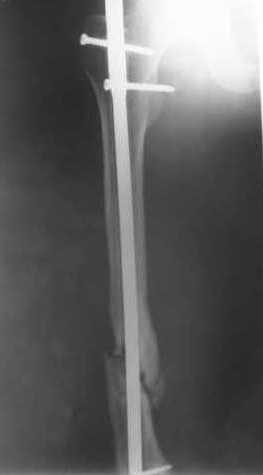

В приложении пример, как их использовали после остеотомии бедра по поводу сросшегося с вальгусом перелома, чтобы не дать гвоздю уйти во внутренний мыщелок.

Да, действительно красивый клинический пример: виден вальгус до операции и последующая коррекция углового смещения на "полярах". Я так понимаю, что в вашей клинике есть возможность использовать различные фиксаторы. Почему не использовали DFN? Спицы какие используете? Киршнера или Илизаровские? С виду очень тонкие...

В приложении пример, дистальный отломок пружинил кзади. Два винта потому, что первый оказался чуть кпереди и не упирался в гвоздь.